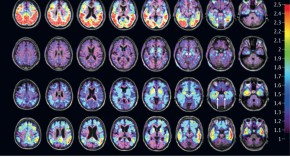

• Progress in the development of PET radiotracers has enabled the noninvasive assessment of the pathological hallmarks of Alzheimer disease (AD) and other neurodegenerative disorders. New reports have revealed the potential usefulness of tau PET imaging in AD and non-AD tauopathies.

• Nobuyuki Okamura

• Kazuhiko Yanai